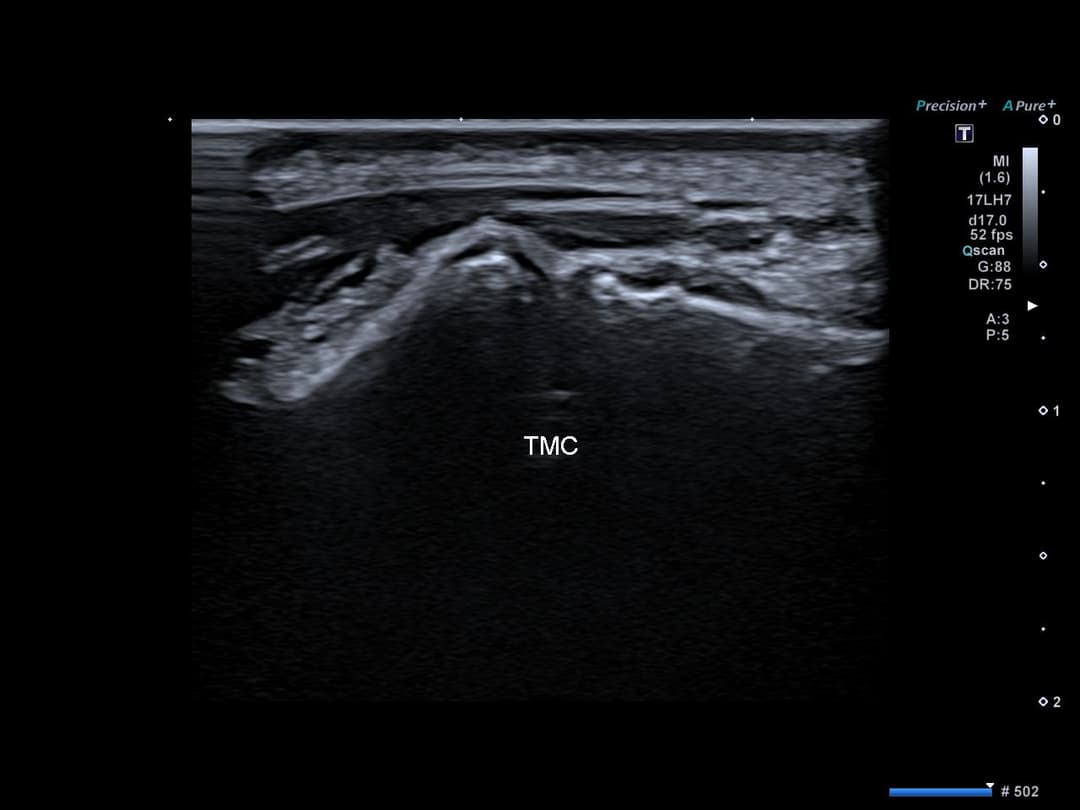

Intégrité de l'articulation trapézo-métacarpienne